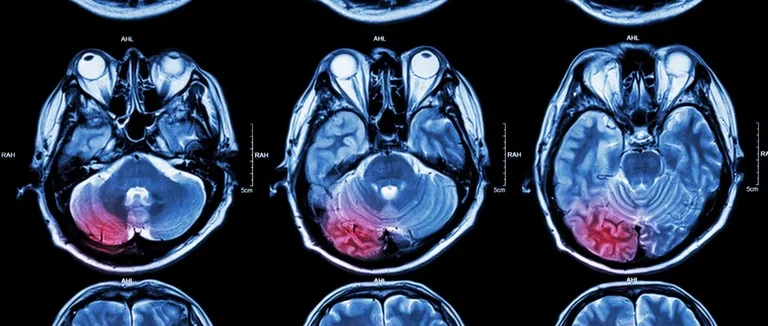

Tests de Tumeur Cérébrale par Imagerie Médicale

Les tumeurs cérébrales sont souvent diagnostiquées grâce à l'imagerie médicale. Ces méthodes permettent de voir le cerveau en détail. Elles aident à trouver les anomalies précisément.

Imagerie par Résonance Magnétique (IRM)

L'IRM est très utilisée pour les tumeurs cérébrales. Elle combine un champ magnétique et des ondes radio pour des images claires du cerveau.

Les avantages de l'IRM sont :

● Des images très détaillées

● Elle trouve les tumeurs tôt

● Elle montre bien les tissus mous